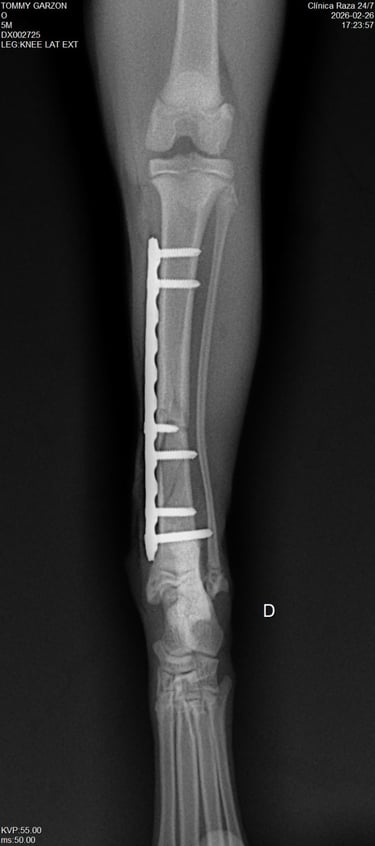

Un sistema de placa bloqueada es una técnica avanzada de fijación interna en la que los tornillos se bloquean directamente a la placa, formando una estructura rígida y estable.

La placa se posiciona sobre el hueso afectado, adaptándose a su anatomía sin necesidad de comprimirlo directamente.

Inserción de tornillos bloqueados

Los tornillos se introducen atravesando la placa y se enroscan en ella, quedando firmemente anclados tanto al hueso como a la placa.

Formación de un sistema rígido

Al bloquearse los tornillos con la placa, se crea una estructura estable tipo “armazón” que no depende de la presión sobre el hueso.

El sistema mantiene los fragmentos óseos alineados, permitiendo una adecuada recuperación y favoreciendo la cicatrización.